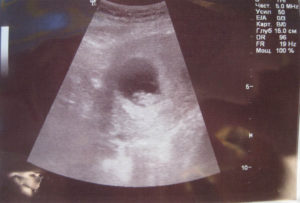

- УЗИ, определяет 8 недель беременности размер плода, состояние кровоснабжения, плаценты и т.д.;

После того как вы сообщите врачу о тревожащих вас симптомах, он назначит вам ультразвуковое исследование. Специалист, который будет делать УЗИ, сможет определить состояние плода, стенок матки. Кроме того, можно определить локализацию спазма, так, он может локализоваться на задней стенке. Не менее часто встречается гипертонус передней стенки.

Для диагностики гипертонуса используется ультразвуковое исследование, при проведении которого может быть выявлен гипертонус задней стенки матки, а также передней. Однако, этот признак не всегда может говорить об угрозе прерывание беременности. Матка может прийти в тонус в ответ на прохождение ультразвуковой волны через ее стенку.